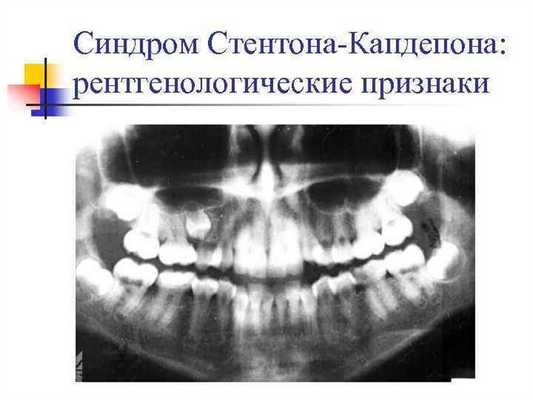

На рентгенограмме у таких зубов выявляются тонкие выпуклые корни, пульпарная камера, небольшая или вовсе отсутствует, корневые каналы узкие, лентовидные. Из-за несовершенного дентиногенеза мезодермалъньтй дефект временных зубов усугубляется. Часто возникает ризрежение костной ткани в периапикальной области, переломы корней зубов, особенно у детей старшего возраста.

На рентгенограмме выявляют снижение высоты корней, сужение полости зуба, облитерацию корневых каналов. Также у пациентов с синдромом Стентона-Капдепона рентгенографически часто обнаруживают периапикальные очаги деструкции костной ткани. Наличие кистозных образований многие ученые связывают не с проникновением инфекции трансдентально при воспалении и распаде пульпы, а с нарушением процессов костеобразования. Результаты ЭОД свидетельствуют о снижении чувствительности пульпы. Дифференцируют синдром Стентона-Капдепона с другими генетически обусловленными пороками развития твердых тканей зубов: несовершенным амелогенезом, 1 и 3 типами несовершенного дентиногенеза, дисплазией дентина. Обследование проводит стоматолог-терапевт. Для выявления наследственных факторов заболевания показана консультация генетика.

На рентгенограмме выявляют снижение высоты корней, сужение полости зуба, облитерацию корневых каналов. Также у пациентов с синдромом Стентона-Капдепона рентгенографически часто обнаруживают периапикальные очаги деструкции костной ткани. Наличие кистозных образований многие ученые связывают не с проникновением инфекции трансдентально при воспалении и распаде пульпы, а с нарушением процессов костеобразования. Результаты ЭОД свидетельствуют о снижении чувствительности пульпы.